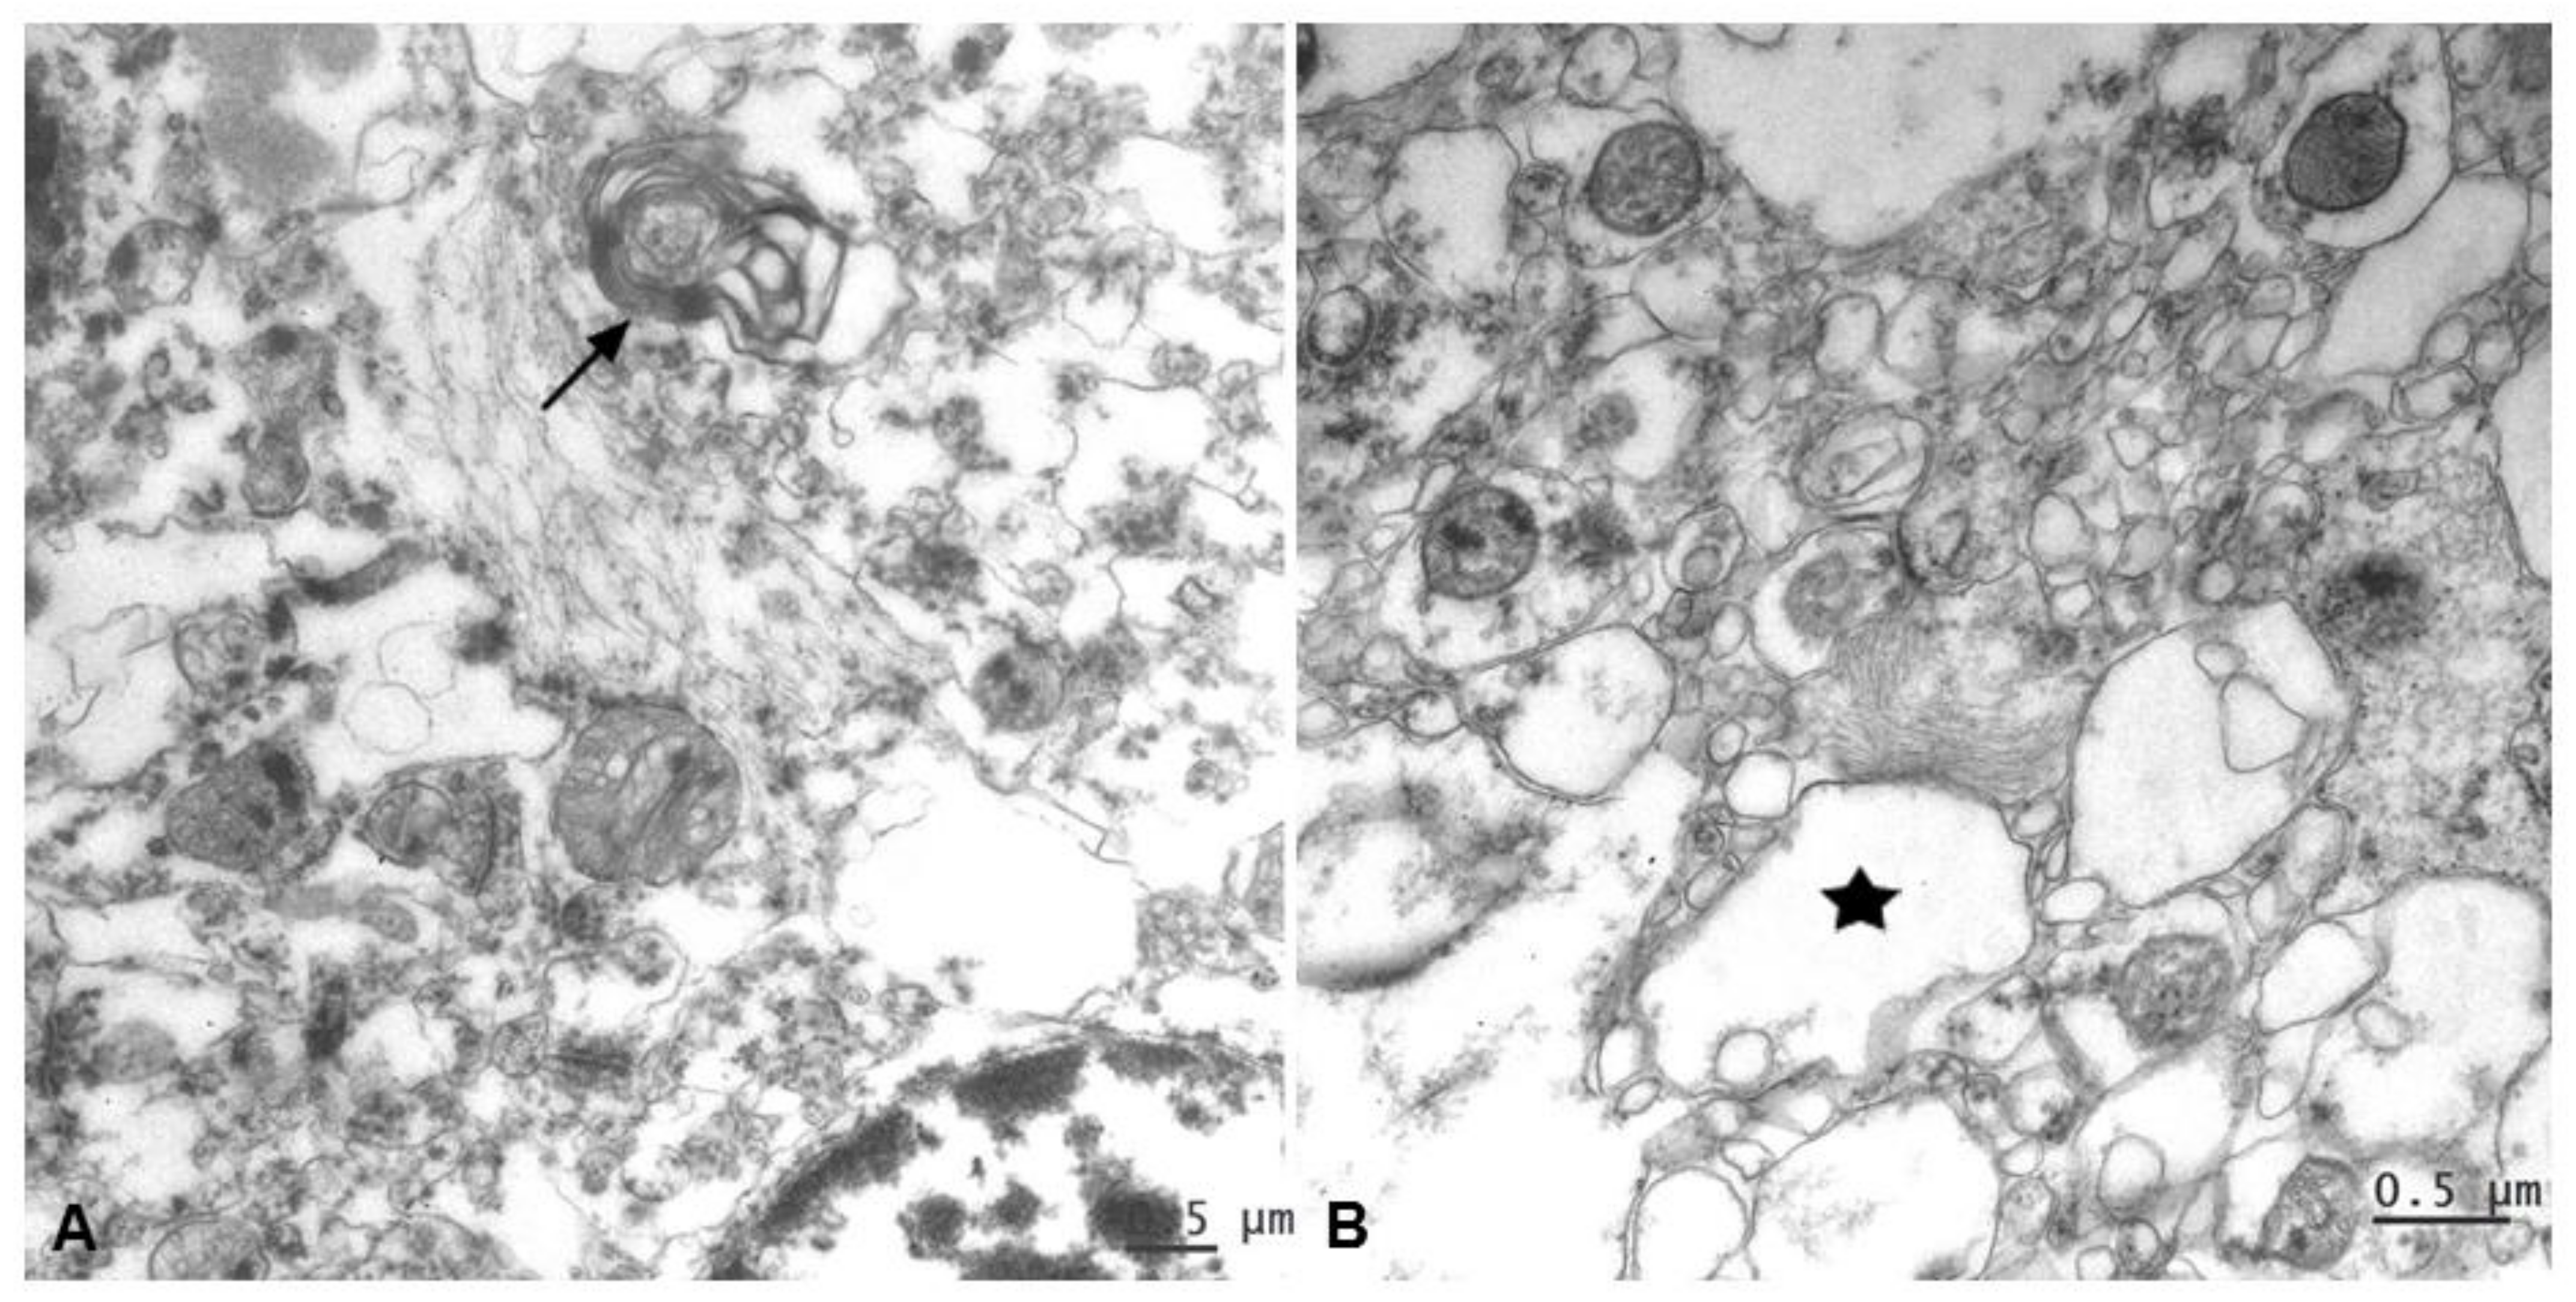

2.3.2. Ultrastructural Findings

Samples showed well-preserved membranes, mitochondria crests, and homogeneous content in the matrix; however, because they came from tissue banks, they showed a much poorer preservation of their ultrastructure in comparison with cases that are fixed with aldehydes. Moreover, it is well recognized that the spongiotic changes associated with the CJD neurodegenerative process result in tissue damage of the sort seen in the micrographs shown here. This makes it harder to distinguish pathologic lesions from fixation artifacts at the sub-cellular level.

Nevertheless, all CJD samples allowed observing distinctive ultrastructural pathological changes of prion disease in relation with intermediate gliofilaments. This cytoskeletal structural filament, as the most characteristic component in astrocytes, was found located in close association with lesions such as vacuolation and alterations of myelin (Figure 8).

Figure 8.

An evident increase of astroglial filaments was found to be associated with two essential neuropathological lesions in prion diseases. (A) Alteration of myelin (arrow) and (B) vacuolation (*, membrane disruption and curled fragments inside).